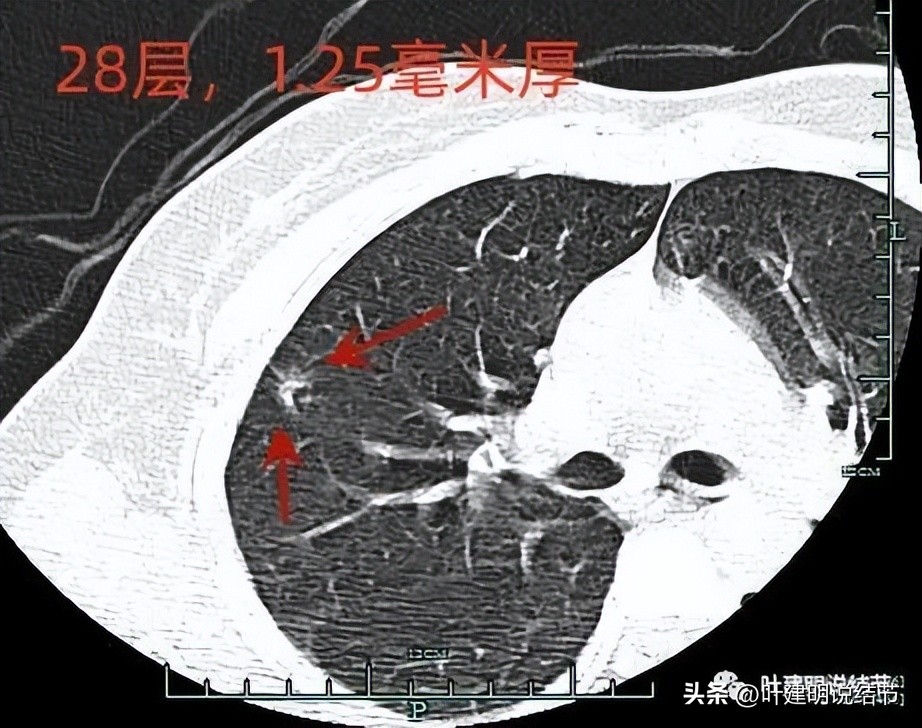

上图示病灶1的定位,红色箭头示病灶1,绿色箭头示定位医用胶。

上两图示病灶2的定位:红色箭头示病灶2,绿色箭头示医用胶。层厚1.25毫米,两者相差5层,也就是说上下相差6.25毫米,术中见到医用胶后,病灶在其下方6.25毫米。